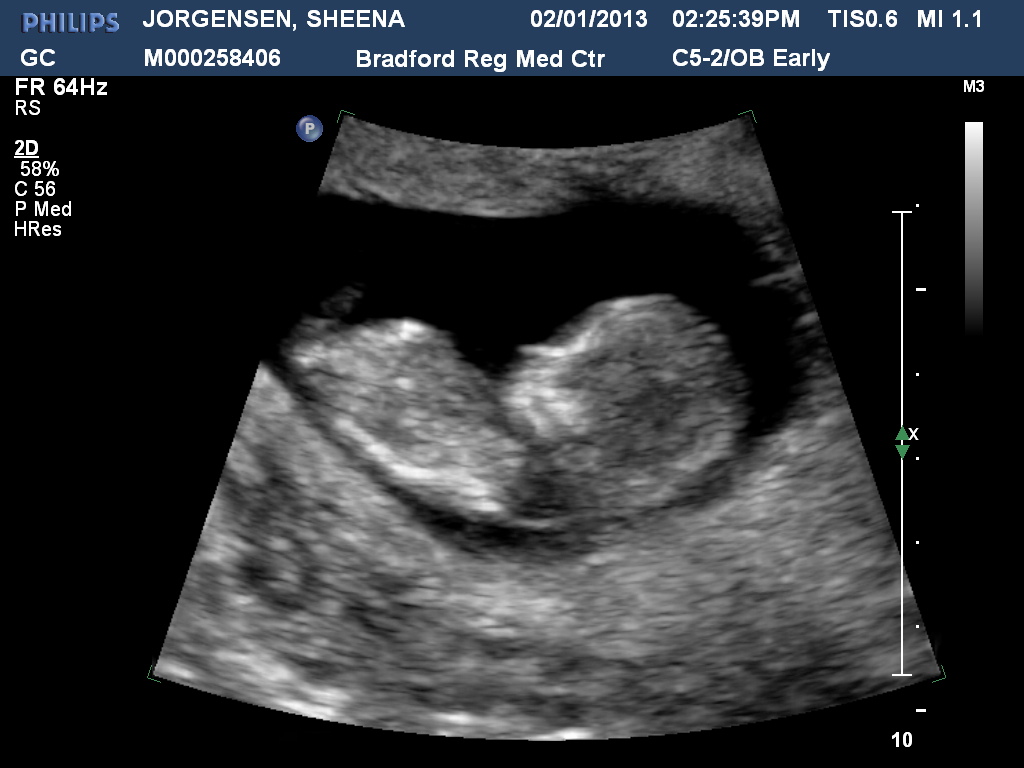

Want to just simulate the Pregnancy Diet?

Get a mild case food poisoning. That lasts for at least 14 weeks.

And yes. Yes I am...